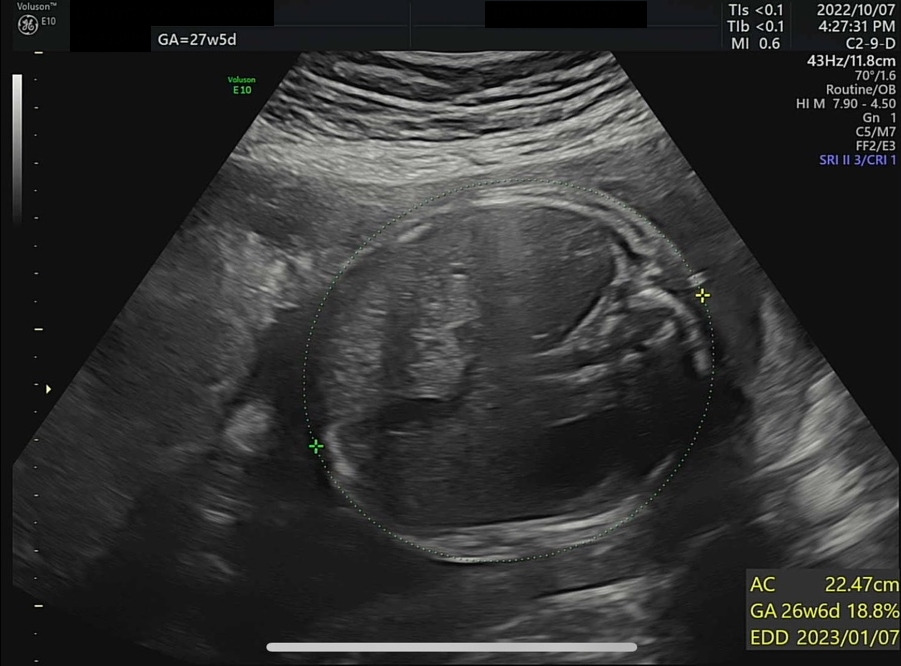

왼쪽부터 복부 둘레, 허벅지뼈 길이와 예상 체중(머리 좌우직경과 복부 둘레로 예측), 팔뚝뼈 길이

KakaoTalk_20221010_121559048_06.jpg 기계는 서양 데이터 기반이라 한국 아기는 이에 비해 머리가 조금 크고 몸통은 좀 작고 다리도 좀 짧다고... (다리는 기니까 다행...)